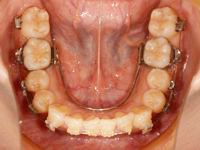

さて、矯正の方は前回全部の歯に装置がついてから1か月が経ちましたが、1か月でこれだけ変わりました![]()

まずは前回の状態です![]()

そして今回の状態です![]()

下の歯の凸凹がかなりとれてきました![]()

今回の調整では、上下ともワイヤーを一旦外して、前回よりも少し太いワイヤーに変えました![]()

今後も調整のたびに少しずつ太いワイヤーに変えて、歯を動かしていきます![]()